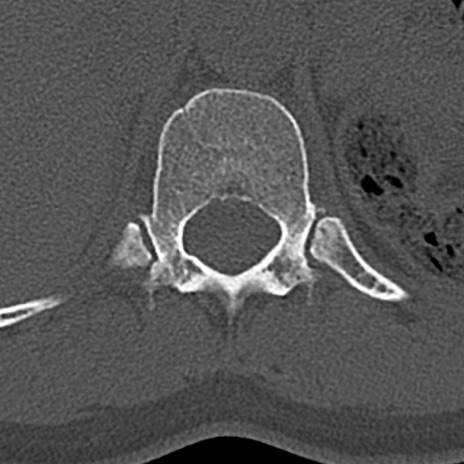

腰椎CT

横断像と矢状断像